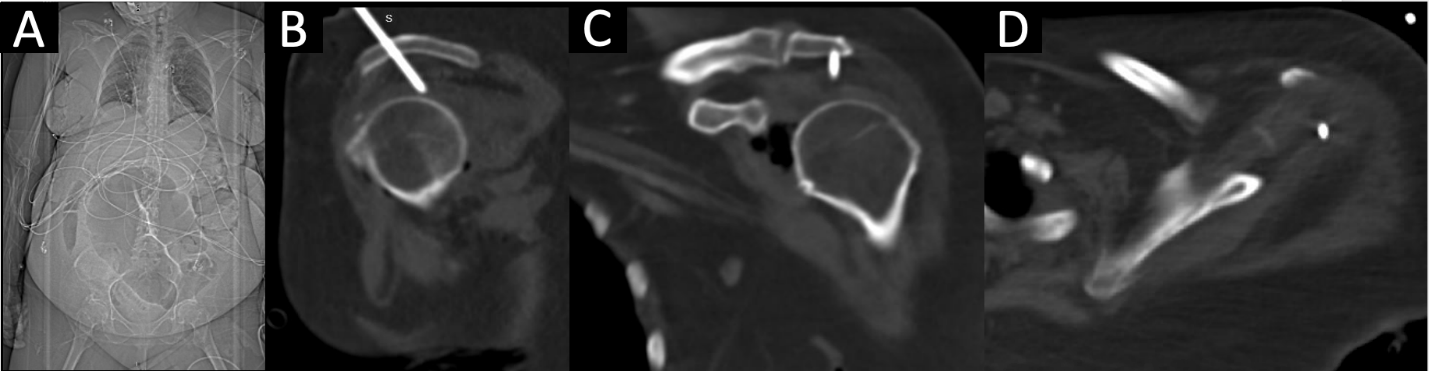

CT imaging from the outside hospital demonstrated a needle-like, radiopaque structure passing through the left acromion and terminating in the glenohumeral joint space, likely representing a malpositioned intraosseous vascular access line (Fig. 4a, b, c, d). Further review revealed challenges with vascular access and placement of a left shoulder intraosseous line that was subsequently removed before transfer to our institution. In light of the patient’s clinical examination, the most parsimonious etiology to the intra-articular and deep posterior scapular musculature emphysema was the malpositioned intraosseous line that pierced the acromion process, such that when the line was utilized, products were administered into the left glenohumeral joint, which traveled medially to the scapula due to the intra-articular insertion of the rotator cuff tendons.

Figure 4: (a-d) Outside hospital scout anteroposterior image of patient’s torso (a) demonstrated a radiopaque structure extending cranially from her left shoulder. Sagittal (b) computed tomography (CT) revealed a needle-like, radiopaque structure traveling cranial to caudal and slightly anterior to posterior through the left acromion process and terminating intra-articularly in the left glenohumeral joint superior to the humeral head. Coronal (c) and axial (d) CT confirm intra-articular endpoint in multiple planes.

NSTI is often a nexus point between critical care, acute care surgery, and orthopedic surgery due to its threat to life and limb caused by the rapid destruction of soft-tissues [7]. NSTI is a rare diagnosis, with an annual incidence of 10 cases/100,000 persons [1]. However, it has been reported to be underestimated in 41–96% of cases [4], largely due to the absence of classic signs – such as bullae, skin necrosis, crepitus, and radiographic emphysema – in over 50% of cases [4,5]. Because NSTI manifests in an extremity in up to 73% of cases [4,7], orthopedic surgery is often the first surgical service consulted. In-hospital mortality remains high, with death in up to 1 in 5 patients with NSTI, which has largely remained unchanged due to the heterogeneity of presentation, challenges of treatment, and limited high-quality evidence [2,3]. Factors associated with poorer outcomes and increased mortality include diabetes, female sex, increased age or comorbidity index, and sepsis at presentation [2,14,15], although up to 26% of patients may have no comorbid risk factors [3]. The most critical factor for improving survival and outcomes in the management of NSTI is the time to surgical exploration and debridement. A recent meta-analysis of 6051 patients with NSTI experienced lower mortality when debridement was performed within 6 hours of presentation [2]. A retrospective study of 295 patients taken for exploration for suspected NSTI revealed a negative exploration rate of 20%; however, the authors advised that surgeons accept this rate of negative exploration to avoid diagnostic delay [16]. In positive cases, rates of amputation are as high as 25% for cases in which debridement alone cannot achieve source control, reconstruction is not possible, or functional status would be superior with amputation [2,7,9]. Factors further associated with limb loss include hypotension at admission, a high glucose level (>300 mg/dL), and a high LRINEC score (>9) [17]. Our case represents a clinical conundrum and diagnostic challenge. Our patient possessed multiple factors associated with poor outcomes, limb loss, and mortality in cases of NSTI [2,13,14,16]. There was overwhelming evidence and precedent in the literature to indicate the patient for operative exploration to exclude NSTI. However, the dissection would have required debridement of the glenohumeral joint, posterior scapular musculature, and chest wall in a critically ill patient, along with a potential forequarter amputation which would have been exceedingly morbid. Although our patient had significant hemodynamic instability and septic shock requiring dual vasopressor support and broad-spectrum antibiotic coverage, laboratory abnormalities, cross-sectional imaging demonstrating deep emphysema, and a LRINEC score of 9, her physical examination was incongruous with NSTI. As demonstrated by our case, it is important to rule out other causes of intra-articular gas before proceeding with surgical exploration. Intra-articular gas or “pneumarthrosis” can be caused by traumatic arthrotomy, closed fracture or dislocation, or prior instrumentation. This patient had no history of recent trauma, and examination of her left upper extremity revealed no apparent wound that would suggest an arthrotomy (Fig. 2). In the absence of penetrating trauma, closed fracture [18,19] or dislocation [20] can cause pneumarthrosis from the vacuum phenomenon of nitrogen gas exchange with distraction or expansion of a closed space [21]. There was no evidence of closed fracture radiographically (Fig. 3a and b), and her glenohumeral joint was concentric on axial CT (Fig. 1a, b, c, d). Finally, prior instrumentation can introduce air into the joint space. After thorough review of outside hospital imaging, it was revealed an intraosseous line was inserted improperly through her acromion process (Fig. 4a, b, c, d), offering a parsimonious, iatrogenic etiology to her pneumarthrosis and deep tissue emphysema. Historically, the proximal tibia has been used for intraosseous access, but the proximal humerus is increasingly favored due to the large volume of the proximal humeral metaphysis that can accommodate higher flow rates [22,23]. Studies evaluating proximal humerus intraosseous access report successful first-pass insertion (>95%) with low complication rates [24,25]. A controlled clinical trial of 29 patients receiving 30 proximal humerus intraosseous lines revealed no major complications and minor complications, including placement failure, poor flow, and catheter dislodgement [23]. However, case reports of adverse events, including a bent intraosseous needle incarcerated in the humeral metaphysis requiring operative removal [26] and iatrogenic humeral anatomic neck fracture [27], have been described.

We add a case to the literature describing improper placement of a proximal humerus intraosseous line through the acromion that led to iatrogenic pneumarthrosis and deep tissue emphysema in the setting of a critically ill patient, causing concern for possible NSTI.